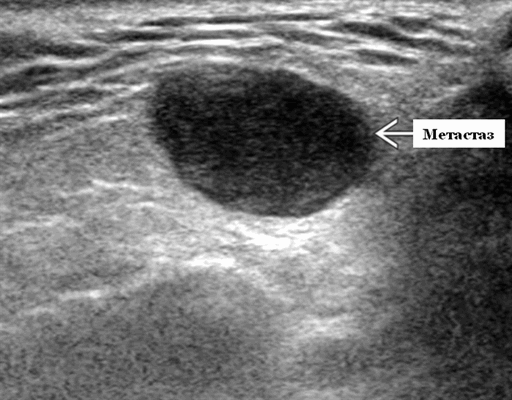

Серошкальное УЗИ. Одиночные или множественные гипоэхогенные образования в известном распределении внутрипаротидных лимфоузлов. Хорошо выраженный или слабо окаймленный (экстранодальное распространение). Экстранодальное распространение. Обратите внимание на местную инвазию интрапаротидной наружной сонной артерии (ВСА), ретромандибулярной вены или экстрапаротидных мягких тканей. Аномальная внутренняя архитектура ± эхогенные ворота. Однородный или неоднородный вид с внутренними кистозными участками в некротических узлах ± метастазы в шейные лимфатические узлы

Метастазы

Слюнных желез очень редко дают метастазы. Первичные опухоли слюнных желез метастазируют в близко расположенные области головы и шеи, а также на более отдаленные части тела. С другой стороны, меланома, рак молочной железы и рак легких могут давать метастазы в интрапаротидные лимфатические узлы. Крайне редко бывают метастазы от рака почки. На УЗИ метастазы могут быть хорошо определены и обычно имеют овальные формы. Иногда довольно трудно на ультразвуком сканировании дифференцировать множественные метастатические поражения от некоторых видов воспаления, синдрома Шегрена и гранулематозной болезни.